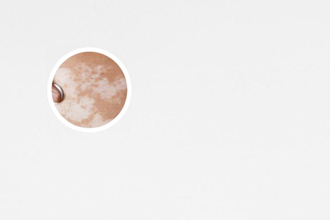

做一次氦氖激光治療白癜風(fēng)的費用并不會很貴,通常幾百元到幾千元不等,具體費用會根據(jù)治療部位的大小、治療頻率以及醫(yī)院的收費標(biāo)準(zhǔn)而有所不同。但是,治療白癜風(fēng)是一個長期的過程,需要持續(xù)治療,因此總的治療費用會比一次治療的費用要高得多。

治療的效果不錯: 氦氖激光可以刺激皮膚中的黑素細(xì)胞,促進(jìn)黑色素的生成,改善白斑的色素沉著。